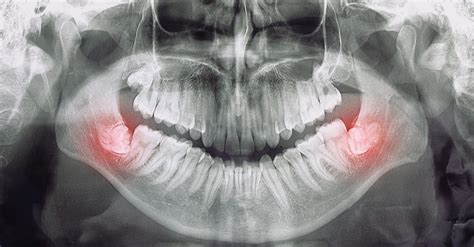

El diagnóstico radiológico es, junto con la exploración clínica, una prueba absolutamente esencial. En la mayoría de los casos, sobre todo en ausencia de una relación directa entre las raíces y el conducto dentario inferior, una ortopantomografía (OPG) y/o una radiografía intraoral serán suficientes para obtener la información necesaria. De no conseguir información concluyente con estas imágenes se puede recurrir a técnicas de imagen tridimensionales como la tomografía volumétrica digital (TVD) o la tomografía computarizada (TC). Dado que no se ha demostrado un beneficio terapéutico claro con la obtención de imágenes tridimensionales preoperatorias se recomienda no incluir estos procedimientos de forma sistemática en los estudios diagnósticos.